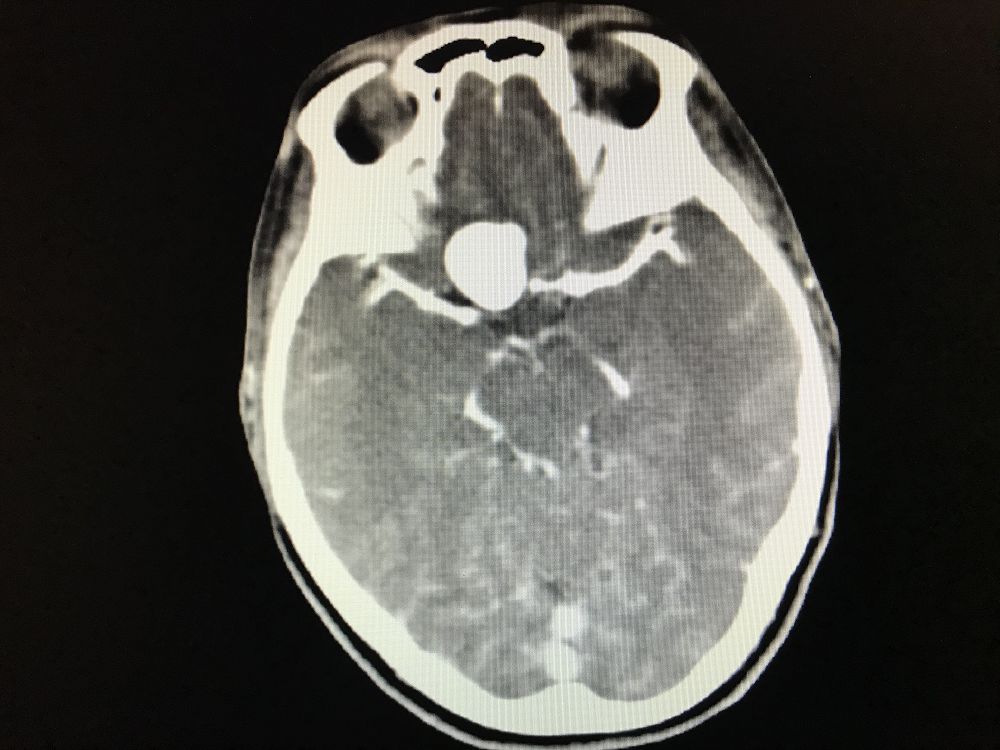

术后复查CT